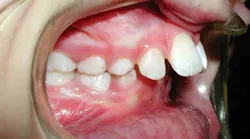

Young children (ages 6–10) with severely protruded upper front teeth, commonly called “buck teeth,” are at increased risk for dental trauma and may benefit from an orthodontic correction, according to a study published recently in the American Journal of Orthodontics & Dentofacial Orthopedics. (1) The study found that approximately 1 in 3 children who were treated for severely protruding teeth were less likely to experience dental trauma (such as a chipped, broken, or knocked out permanent tooth).

“Protruding front teeth cause other problems for children. The ‘bite’—the manner in which the upper and lower teeth meet—may be improper, and make it difficult for a child to bite food or to chew properly. The condition can interfere with speech for some individuals. And there’s an emotional toll, too, for children who may be bullied because of their teeth,” says Dr. Poole. “Interceptive treatment addresses the immediate protrusion problem. Parents need to know that most patients will require a second phase of treatment after most or all of their permanent teeth are in to move teeth into their final, optimal positions.”

“Parents should also understand that children go through what we call an ‘ugly duckling’ phase, when permanent teeth begin to emerge and seem too large or appear to be spaced incorrectly,” Dr. Poole says. “Most children will ‘grow into’ their teeth and go through this phase without the need for orthodontic treatment. But for those children whose teeth protrude significantly, I recommend parents take their child to an orthodontist for an evaluation.”